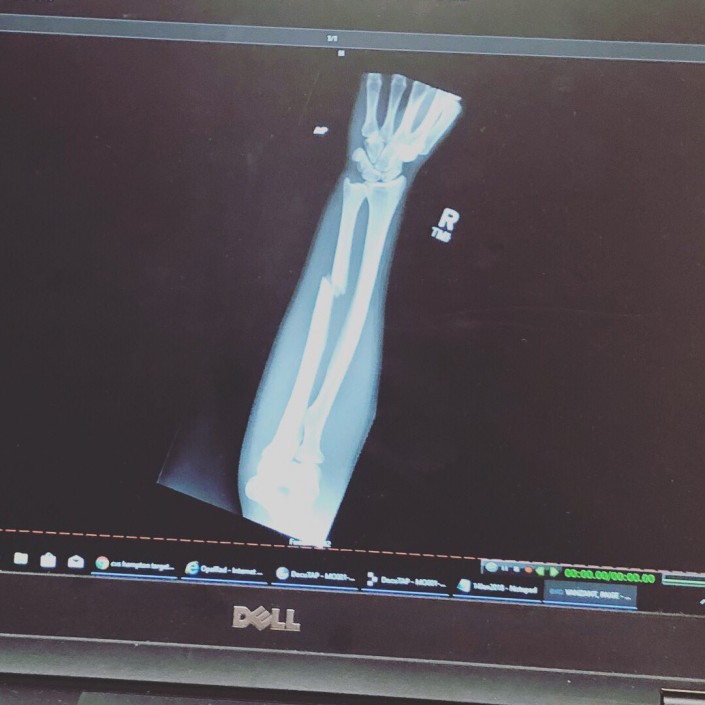

Позже пострадавшая участница соревнований опубликовала в соцсетях фотографию из больницы и рентгеновский снимок сломанной конечности.

© Twitter/PaigeVanzant